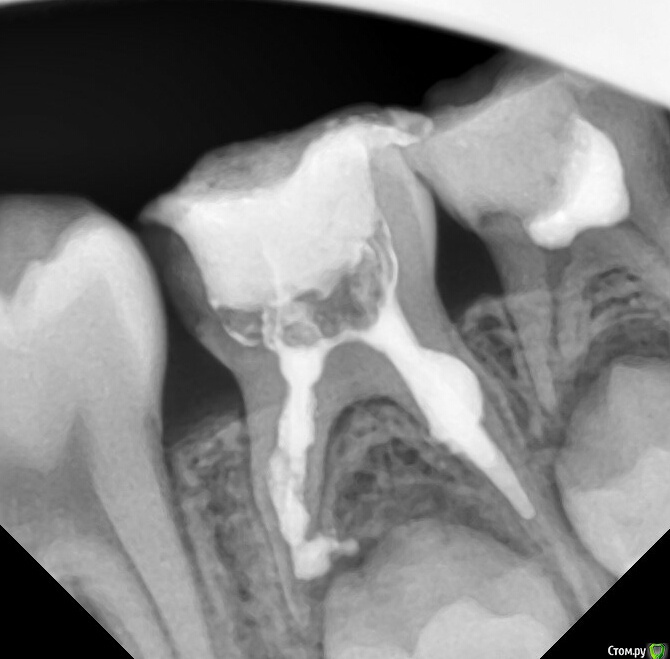

anytka Опубликовано 14 октября, 2015 Поделиться Опубликовано 14 октября, 2015 (изменено) 1.6 направила на удаления т.к вижу на снимке трещину между щечным кормить хирург сказал лечить. Толи он не видит. Толи я вижу что то не то. Просто получить так. Что снимок сделали у нам в поликлинике. А хирург у нас в отпуске. И я отправила в другую стоматологию на удаления к хирургу. Тот вызвал детского стоматолога, и терапевта и они пришли к мнению что надо лечить т.к ребёнок удалять жалко. Девочке 15 лет. А лечить они вернулись ко мне почему-то Изменено 14 октября, 2015 пользователем anytka Ссылка на комментарий

CRAZYDUCK Опубликовано 15 октября, 2015 Поделиться Опубликовано 15 октября, 2015 (изменено) 1.6 направила на удаления т.к вижу на снимке трещину между щечным кормить хирург сказал лечить. Толи он не видит. Толи я вижу что то не то. Просто получить так. Что снимок сделали у нам в поликлинике. А хирург у нас в отпуске. И я отправила в другую стоматологию на удаления к хирургу. Тот вызвал детского стоматолога, и терапевта и они пришли к мнению что надо лечить т.к ребёнок удалять жалко. Девочке 15 лет. А лечить они вернулись ко мне почему-тоНу , если им ЖАЛЬ, то пусть в той клинике детский стоматолог и лечит, скажите, что у Вас нет методик, позволяющих спасти этот зуб. Не знаю всей картины, но родителям почему-то не жаль было своего ребенка , раз уж до такого довели... Изменено 15 октября, 2015 пользователем CRAZYDUCK 5 Ссылка на комментарий

shevchenko.dr Опубликовано 11 ноября, 2015 Поделиться Опубликовано 11 ноября, 2015 при таком разрушении 16 - надо удалять. потом ортодонтически возможно сдвинуть 17 и 18 "на один вперед". и будут полноценные зубы вместо безнадежного шестого. возможно в будущем и без имплантации обойдется! 1 Ссылка на комментарий